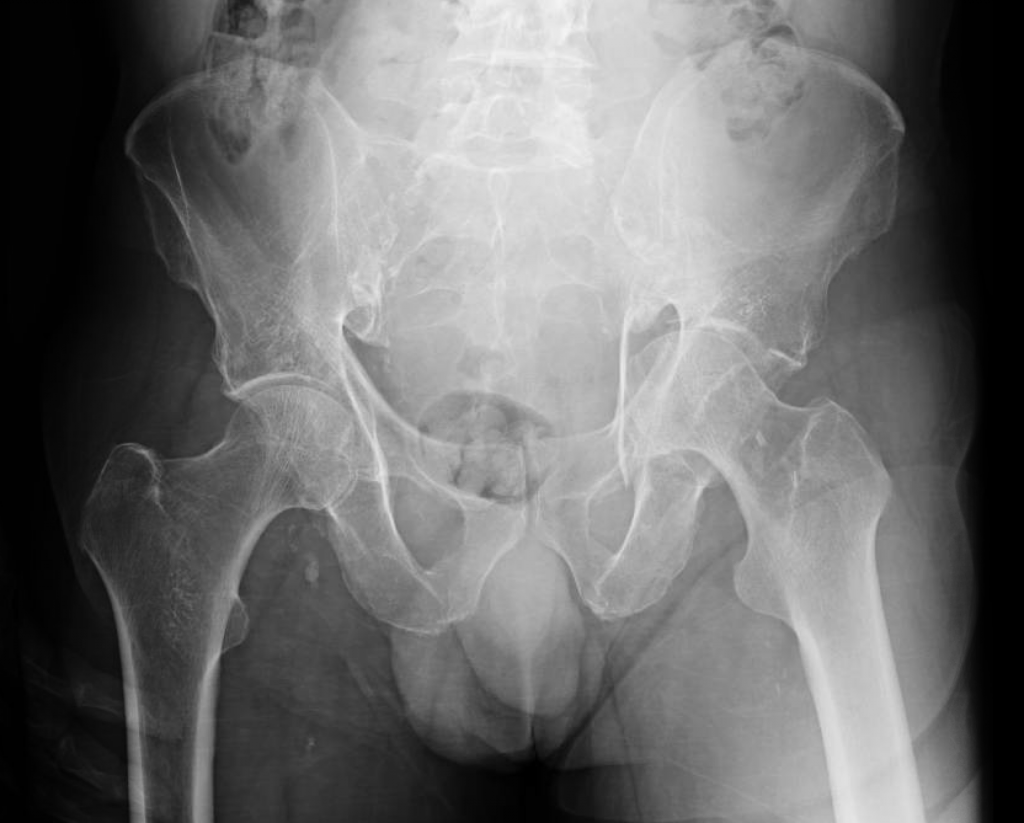

This is a 78 year old male who fell and sustained an anterior column acetabular fracture. The patient had a history of peripheral vascular disease and previously underwent femoral-femoral artery bypass. This precluded him from having a traditional open reduction internal fixation (ORIF) of the acetabulum through an ilioinguinal approach.

The patient underwent simultaneous acetabular ORIF and complex THA reconstruction by Dr. Darwin Chen and Dr. David Forsh (Chief of Orthopaedic Trauma). A Kocher-Langenbeck approach was used for exposure. The anterior and posterior columns were secured together using a single posterior-to-anterior screw just superior to the acetabulum. An acetabular shell was implanted with excellent inherent stability, followed by screw fixation into the superior dome as well as inferiorly into the ischium.